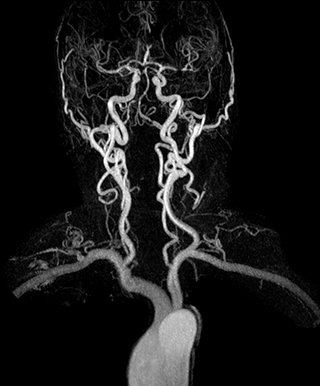

3D dynamic MRA of head and neck

Excellent image quality is obtained in this dynamic scan., C-SENSE factor 5.4, scan time is 1:20 min, voxel size is 0.8 x 0.8 x 1.6 mm, Ingenia Ambition, 1.5T.